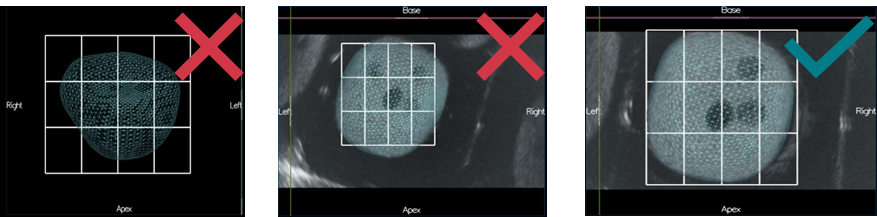

d. Probe pressure and image

- Lobes exceed ultrasound image (top left image) → gland deformation due to excessive pressure on the prostate.

- Prostate is too far from the probe head (top right image) → not enough pressure.

- White lines of probe head have to be continuous.

- The ultrasound image must not have black continuous line (ultrasound noise).

e. Bounding Box not well adjusted

Reviewing the grid allows to check the bounding box adjustement : It must fit correctly with the prostate contour.